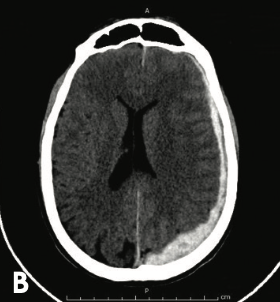

Estudios de imagen: Hematoma subdural

A

Forma de semiluna o plátano

Origen venoso

Evolución lento

Por debajo de la dura madre y por encima de la aracnoides

Puede atravesar subduras

Presencia de lesión parenquimatosa concomitantes